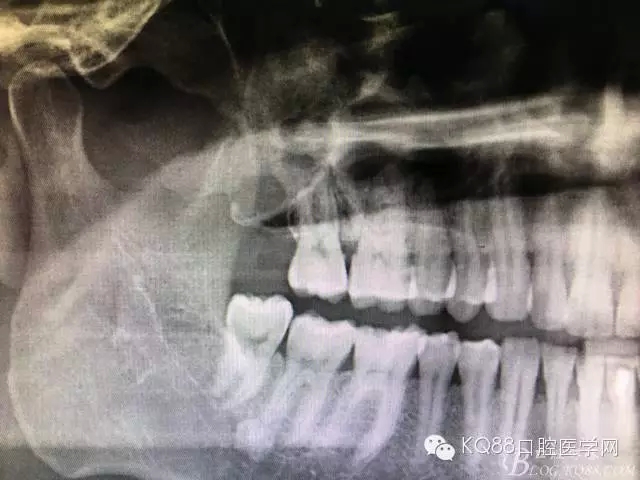

圖18.術后的全景片影像檢查:

圖19.局部放大影像檢查:17牙根未見損傷